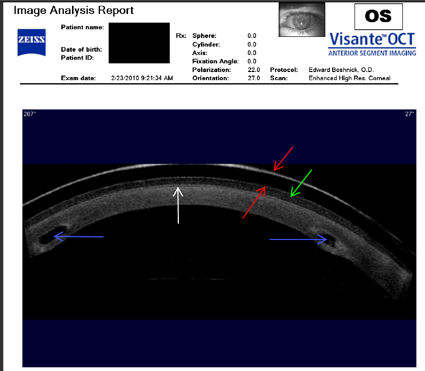

Следующие изображения были получены с использованием метода, называемого оптической когерентной томографией, или ОКТ. Прибор позволяет получить изображение в поперечном сечении путем сканирования передней части глаза (переднего сегмента) лучом света. Думайте об этом как об ультразвуке, использующем свет вместо звуковых волн для создания изображения живых тканей.

У пациентки, описанной ниже, развилась эктазия роговицы после операции LASIK, и ее лечили с помощью ПОТРЕБЛЯЕМЫЕ ВЕЩЕСТВА . Противоположные красные стрелки указывают на переднюю и заднюю поверхности склеральной линзы, которую носит пациент. Зеленая стрелка указывает на заполненное жидкостью пространство между линзой и роговицей. Белая стрелка указывает на заднюю поверхность лоскута LASIK, который никогда не заживает. Синие стрелки указывают на два INTAC, которые имплантированы в роговицу. Тот факт, что пациент сейчас носит склеральные линзы, указывает на то, что имплантация INTAC не привела к восстановлению функционального зрения. Нажмите на изображение, чтобы увеличить.